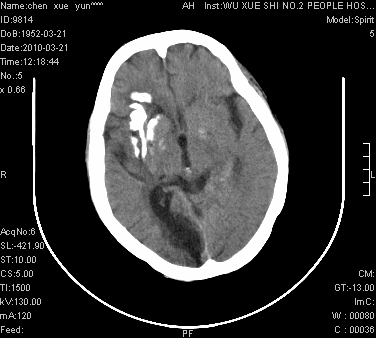

性别:不详;年龄:58岁;病史:不详。

ct表现:1、右侧额颞叶深部不规则钙化密度团块,呈弯曲条带状,占位效应不明显,考虑少枝胶质细胞瘤可能性大于血管瘤。2、右枕叶大片不规则低密度影,密度近似于脑脊液,右侧侧脑室后角及三角区扩张,考虑为陈旧性脑梗塞。

讨论:1、这个病灶的钙化有点像脑回样钙化,因此我最初考虑颅面血管瘤病(sturge-weber综合征),但是查阅了我们网站上的几个颅面血管瘤病病例,钙化均位于脑实质表面,沿脑回分布,而这例病灶位置较深,因此可以否定“颅面血管瘤病”这个诊断。

2、卜一会员曾经说过:少枝胶质细胞瘤的典型征象为弯曲条带状钙化,可作为定性的可靠征象(http://www.radida.com/news_view.asp?id=5150)

3、血管瘤也可以出现弯曲条带状钙化,但血管瘤多数出现“负占位”效应,即病灶周围的脑室、脑池及脑沟不是受压变窄,而是局限性的增宽。